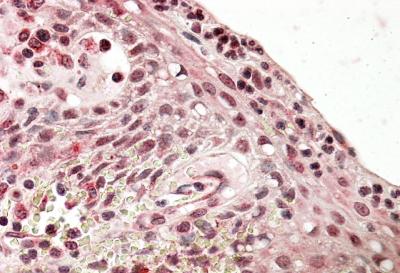

APG00624G (3.8 μg/ml) staining of paraffin embedded Human Tonsil. Steamed antigen retrieval with citrate buffer pH 6, AP-staining. |